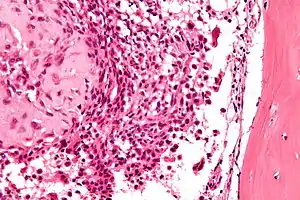

| عکاسی ریزنگاری از یک کندروبلاستوما. | |